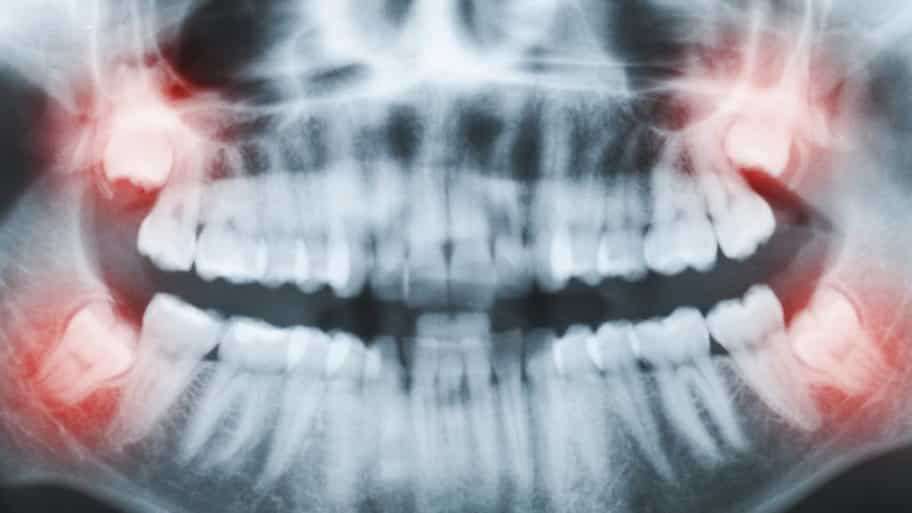

One of the only ways to prevent severe oral fitness complications is thru timely care such as Wisdom Teeth Infection Treatment. Wisdom teeth are the very last set of molars to erupt, and they frequently cause demanding situations, including crowding, pain, and rot.